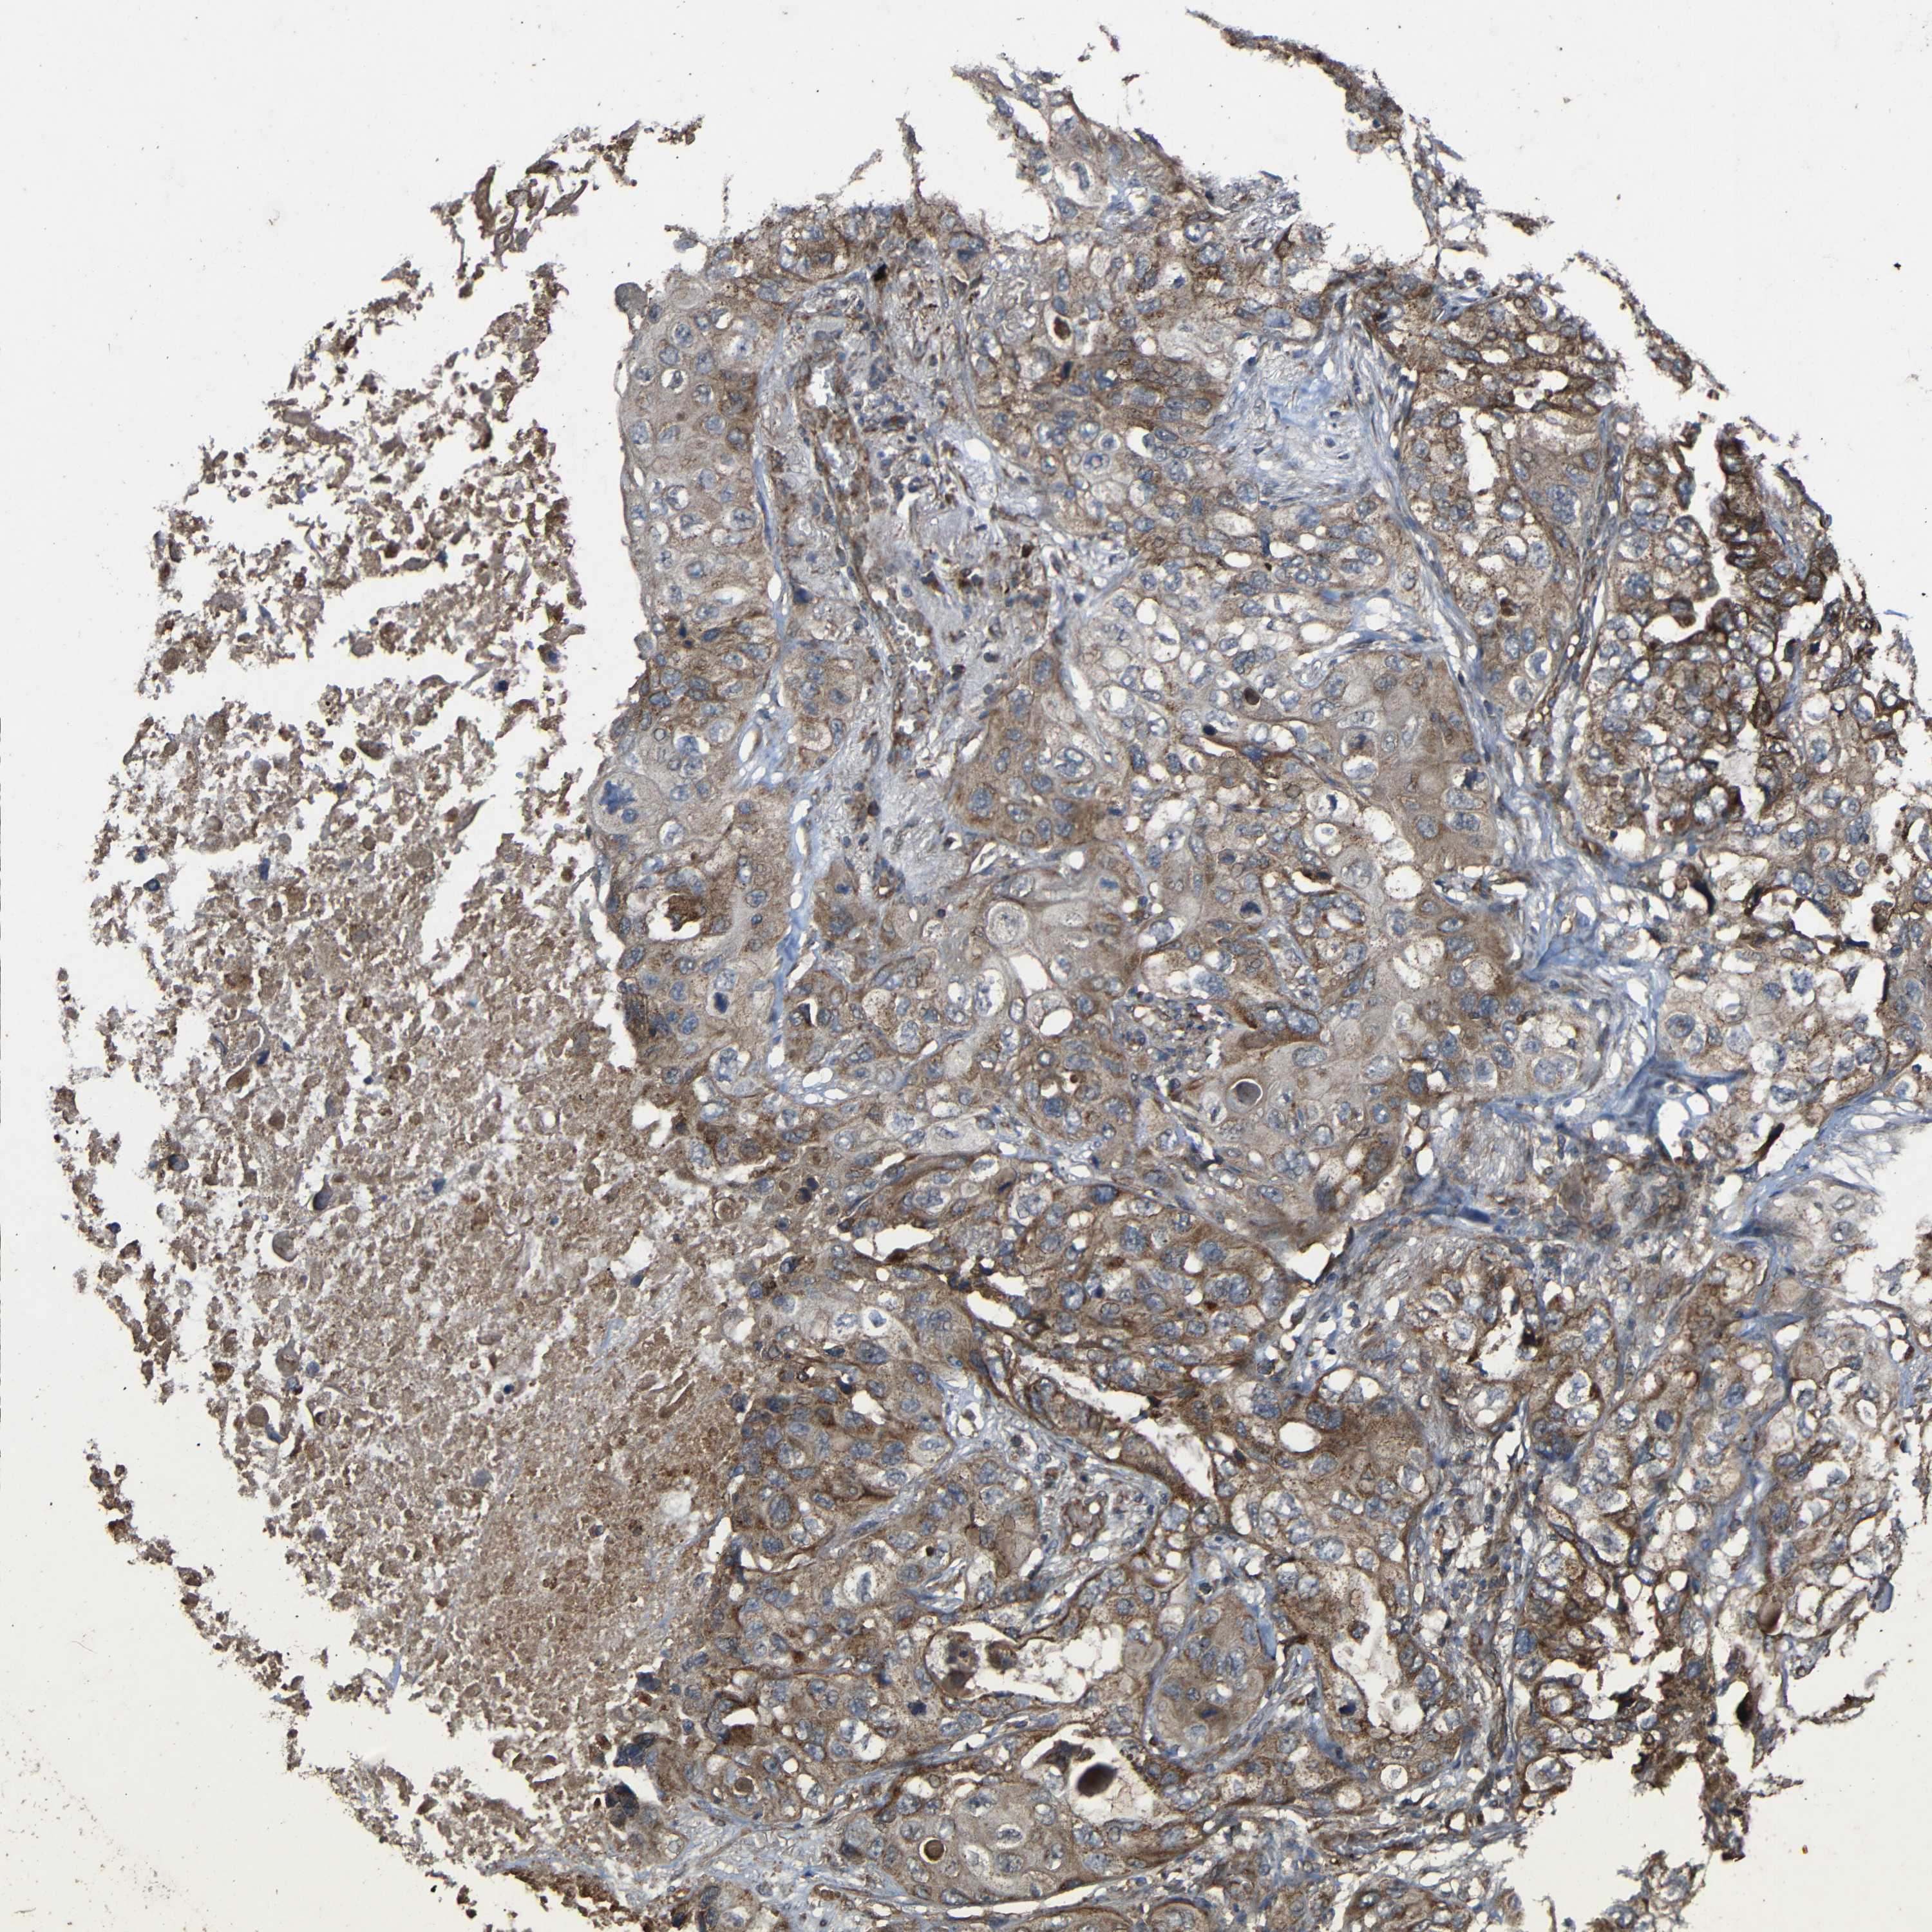

CANCER LUNG CANCER Show tissue menu

LUAD TCGA LUAD VALIDATION LUSC TCGA LUSC VALIDATION PROTEIN LUAD CPTAC PROTEIN LUSC CPTAC PROTEIN EXPRESSION